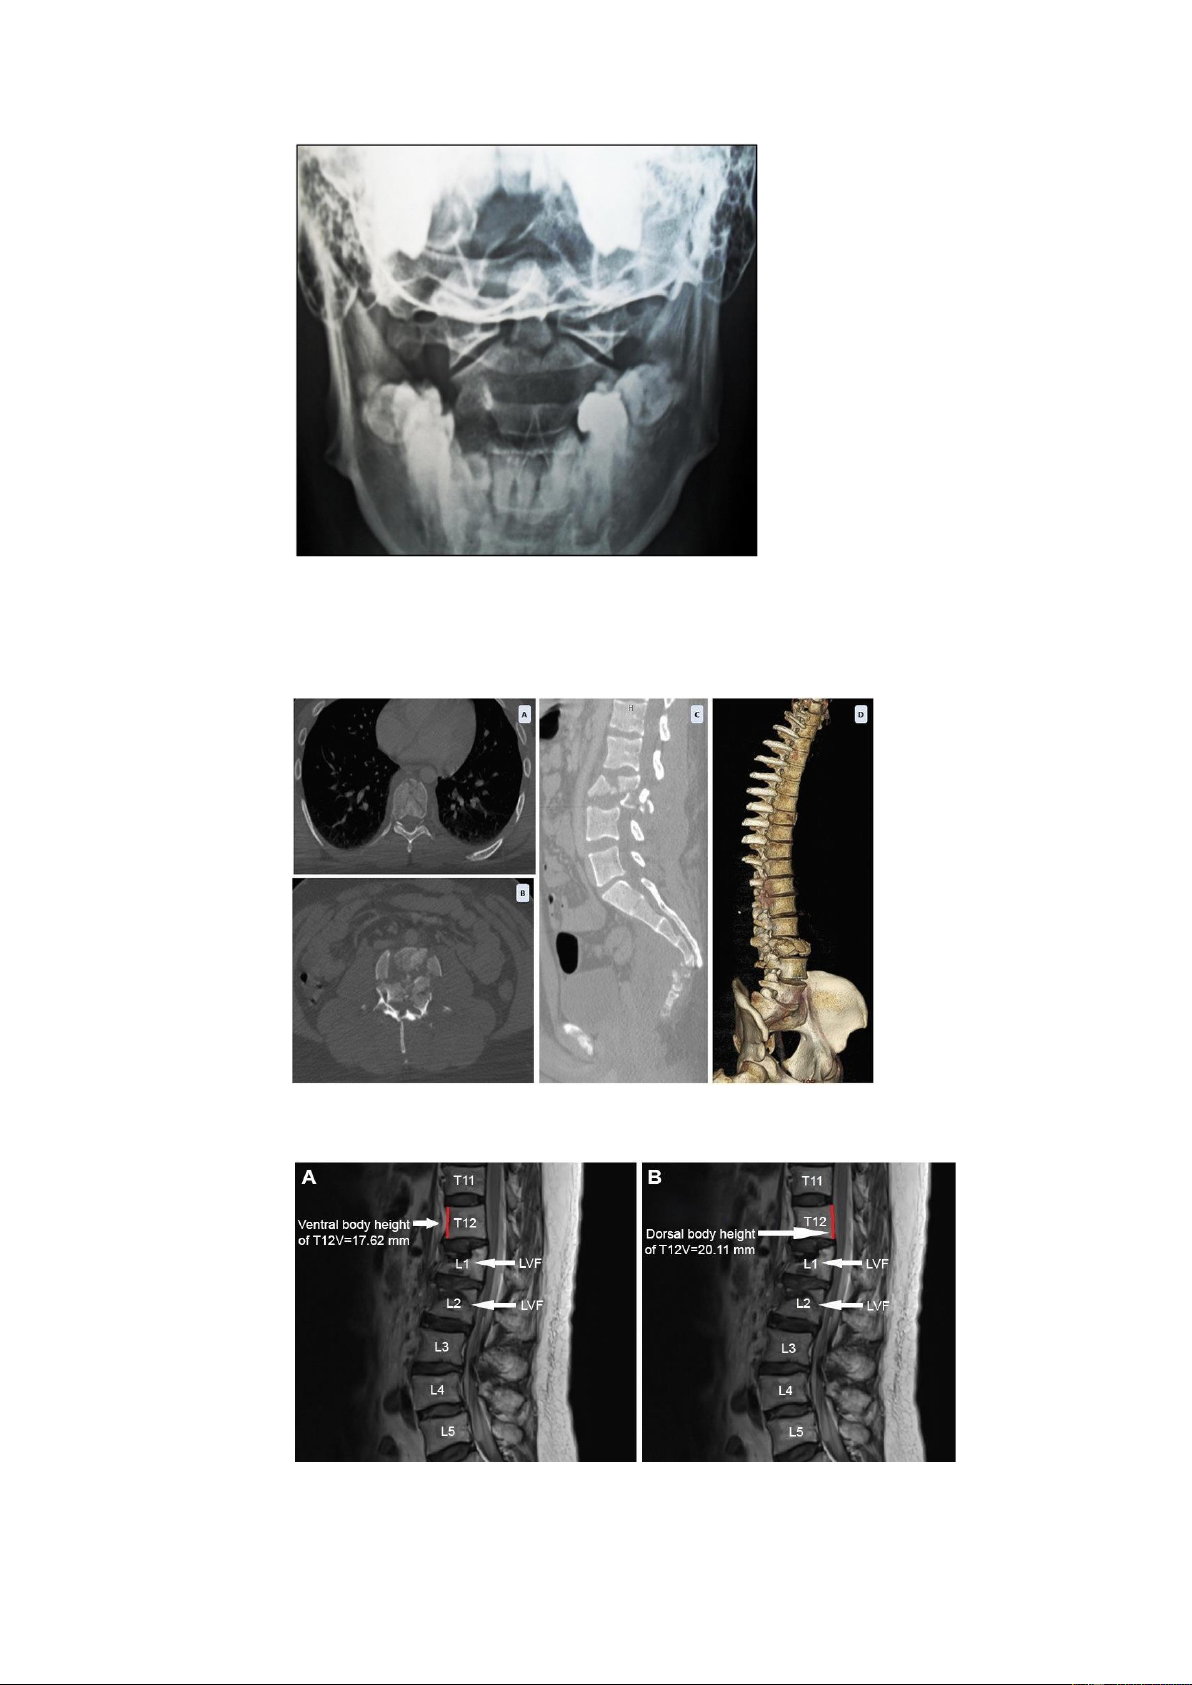

• Chụp CT để kiểm tra những tổn thương xương, mức độ mất vững của cột sống

• Chụp cộng hưởng tử để xác định những tổn thương tủy, màng tủy,

đĩa đệm, rễ thần kinh, các dây chằng V. Tiên lượng: 1. Phục hồi thần kinh: lOMoAR cPSD| 39651089